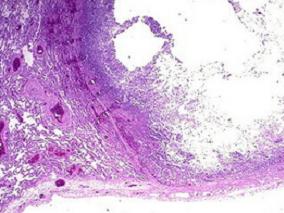

1小时条评论一、病史摘要 患者,男性,27岁,因反复咯血26天于2009年10月5日入院。患者于2009年9月9日修车时突然出现咯血,量约250ml(1~2次),鲜红色,无发热、咳嗽、咳痰、气促及胸痛等不适,就诊于当地县人民医院,胸片示右下肺不张(图120‐1),予以垂体后叶素等药物治...